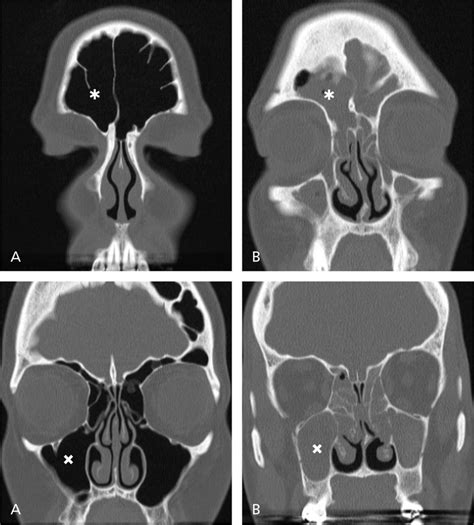

Nasal polyps often return after treatment, so steroid nasal sprays can be used daily to prevent recurrence. A nasal polyp is a benign (noncancerous) tumor that grows from the lining of the nose or sinuses. They usually occur in both the right and left nasal passages and can block the flow of air. The most common symptoms they cause are a stuffy, runny nose. Nasal polyps are benign (noncancerous) growths that may form inside nasal passages and sinuses — the spaces behind your nose and cheeks. Nasal polyps are painless soft growths inside your nose. Broadly defined, nasal polyps are abnormal lesions that originate from any portion of the nasal mucosa or paranasal sinuses. Nasal polyps usually grow in the shape of a teardrop.

With nasal polyps, specifically, it's possible the cause is an increase in inflammation and swelling of the nasal passage. Nasal polyps are noncancerous growths that develop in the lining of the nose and surrounding sinuses. They are also usually triggered by chronic inflammation and are associated with a number of health conditions. They may also experience heavier than normal bleeding during their periods or spotting between periods. They result from chronic inflammation and are associated with asthma, recurring infection, allergies, drug sensitivity or certain immune disorders. Nasal polyps usually grow in the shape of a teardrop. A nasal polyp is a benign (noncancerous) tumor that grows from the lining of the nose or sinuses. Nasal polyps grow in inflamed tissue of the nasal mucosa. If polyps grow larger, however, you. Read about the symptoms, causes, treatments and when to see a gp. Nasal polyps can grow anywhere on the lining of the nose or the sinuses. How to cure nasal polyps naturally. They're not usually serious, but they can keep growing and block your nose if not treated.

How to cure nasal polyps naturally. This type is by far the most common and is exemplified by the picture above. They're not usually serious, but they can keep growing and block your nose if not treated. Nasal polyps are growths that result from inflamed mucous membranes in the sinuses and nasal passages. Nasal polyps are a side effect of some other health condition — most often allergies or an infection from a virus or bacteria. Polyps are an end result of varying disease processes in the nasal cavities. They hang down like teardrops or grapes. They are also usually triggered by chronic inflammation and are associated with a number of health conditions. Nasal polyps grow in inflamed tissue of the nasal mucosa. It helps a lot even though it is hard because otherwise she is still her normal dog self and very healthy in all other. Nasal polyps are a result of ongoing (chronic) rhinosinusitis. Nasal polyps can grow anywhere on the lining of the nose or the sinuses. Nasal polyps are painless soft growths inside your nose.